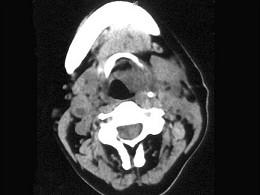

问题 女,54岁,鼻咽部异物感约3个月,PE:左侧声带固定,可见肿物,CT如图所示,应诊断为 ( )

选项 A、慢性增生性喉炎 B、增生型喉结核 C、喉癌 D、喉部血管瘤 E、喉部乳头状瘤

答案 C